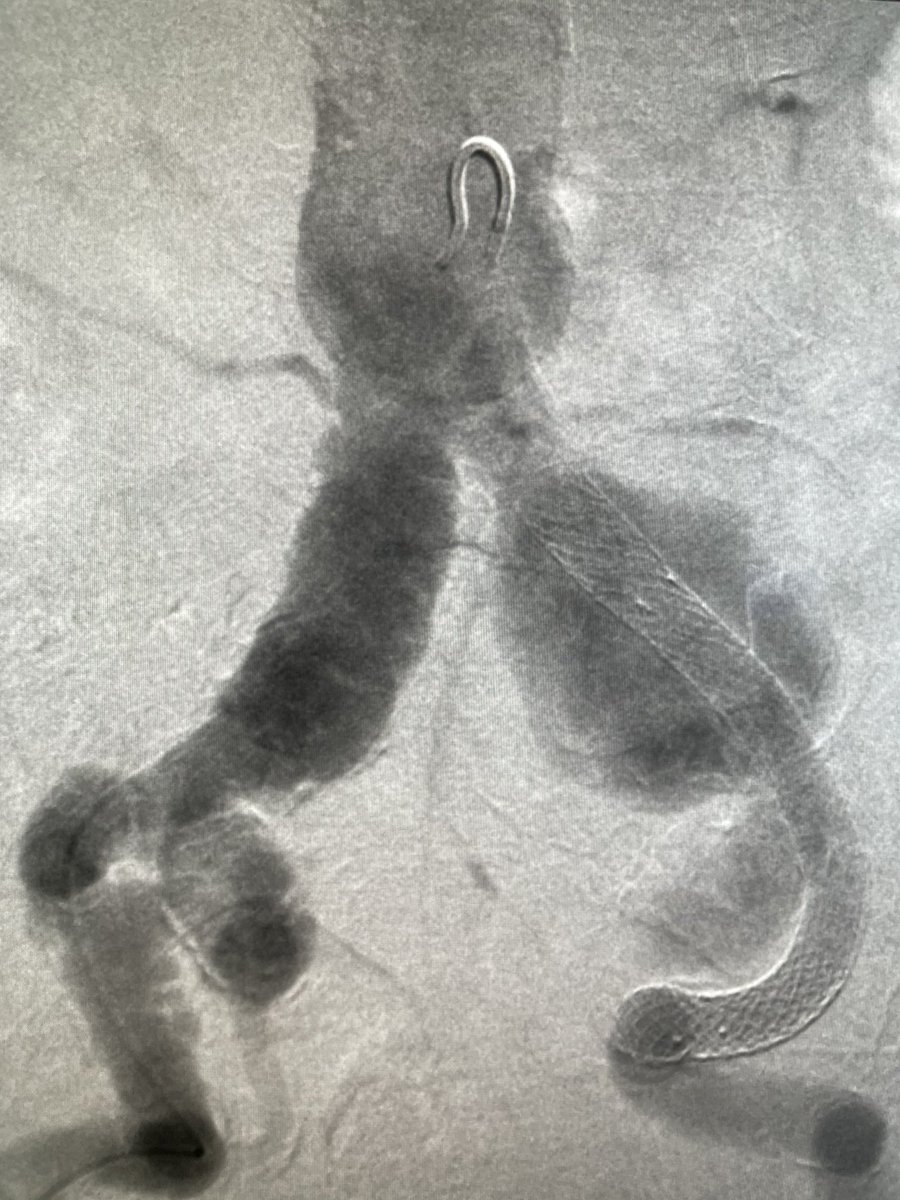

@ChengaziMD @t_intheleadcoat @SDhandMD @drochohan @kmadass @JayMathewsMD @CHICKVIR @Dr_Sudi @DrJayMohan @hkdamonster @SyedYNaqvi1 Nice save with minimal XR, a little IVUS as well? Lucky to have your expertise. I’ve also been preferring IJ when possible